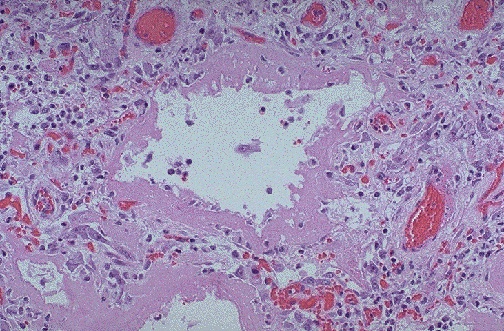

The microscopic appearance of the lung is seen here at high magnification. Note the pink hyaline membranes and the type II cell hyperplasia.